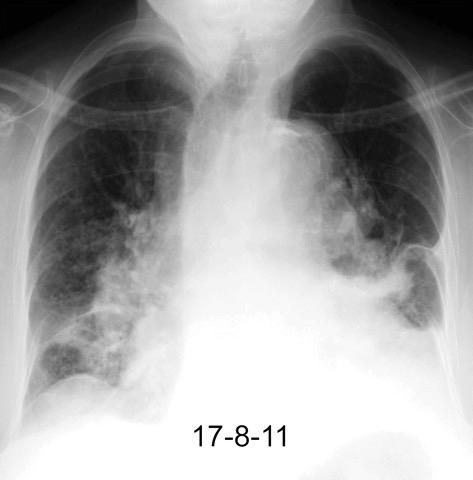

Ganglios retroperitoneales (flechas negras)

germinales del testículo izquierdo Nódulos pulmonares múltiples. (flechas verdes). Ganglios paratraqueales. (flechas amarillas). Dudoso ensanchamiento retrocrural (flechas negras)

Panda A et al. “Straddling Across Boundaries”. Thoracoabdominal Lesions: Spectrum and Pattern Approach. Curr Probl Diagn Radiol, 2015